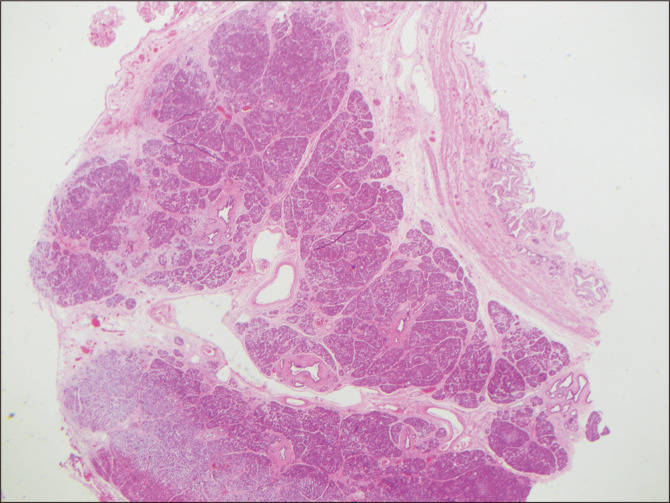

Heterotopic pancreas (HP) refers to the presence of ectopic pancreatic tissue located outside of the normal pancreatic location without anatomical or vascular continuity with the pancreas. HP within the gallbladder (HPGB) was first described by Otschkin in 1916. It remains an exceedingly rare pathology with few reported cases. Here we describe a case of HPGB in a 42-year-old female following laparoscopic cholecystectomy for symptoms of biliary colic. She presented with epigastric pain, elevated levels in liver function tests, and gallbladder sludge on ultrasound. Her lipase and bilirubin levels were within normal limits. Histopathological assessment of the gallbladder identified mild chronic cholecystitis and pancreatic heterotopia adjacent to the cystic duct of the gallbladder with all three elements (ducts, acini, and endocrine islets) of the pancreas, consistent with type 1 based on the classification of Gaspar Fuentes et al. HPGB is often diagnosed incidentally during histopathological examination after cholecystectomy. Preoperative diagnosis is challenging due to its rarity. It is thought to be asymptomatic. Although the clinical significance of HPGB remains uncertain, it has been hypothesized that HPGB can cause acalculous cholecystitis and also have the potential for malignant transformation. Our case supports the theory that the exocrine function of an ectopic pancreatic tissue may contribute to chronic inflammation in the gallbladder. In conclusion, although HPGB is a rare finding with unclear clinical relevance, its potential for malignancy and association with cholecystitis warrant further investigation. Given its scarcity, most knowledge about HPGB comes from case reports and case series. This report adds to the existing literature.